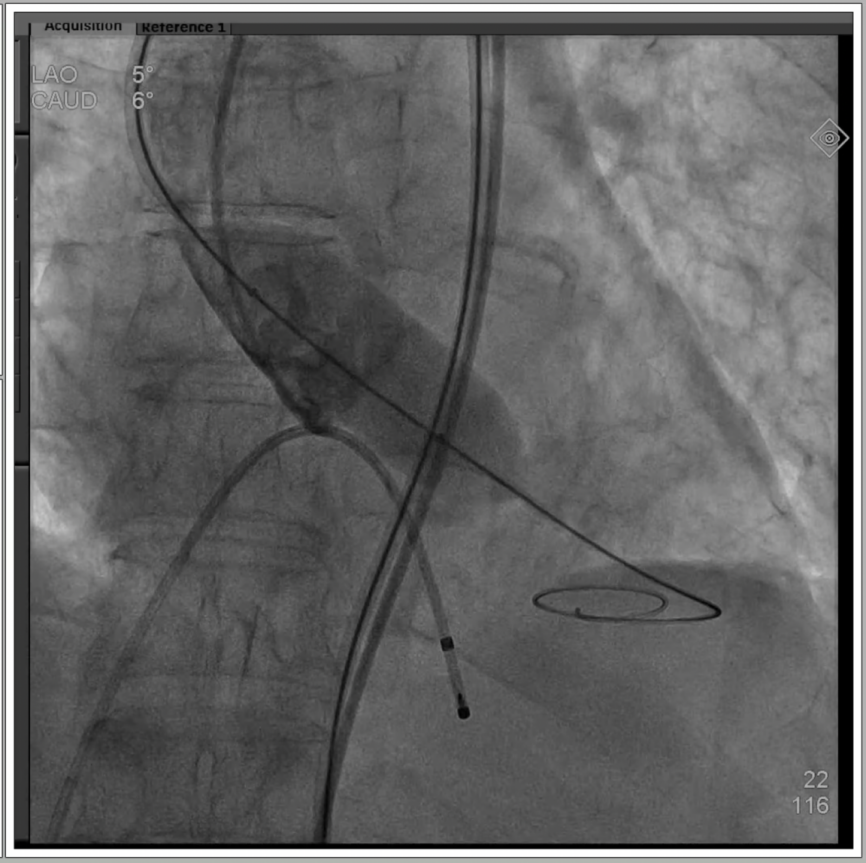

1、全麻下建立双侧股动脉入路,以右股动脉为主;血管穿刺后置入14F eSheath血管鞘。

2、导丝跨瓣后置换猪尾导管,测量主动脉瓣压差40mmHg;

3、使用20mm球囊进行预扩,无腰征无反流,两侧钙化被球囊推开。

4、通过支撑导丝,送入23mm SAPIEN 3瓣膜,使用独特调弯功能,保证安全过弓并成功跨瓣;